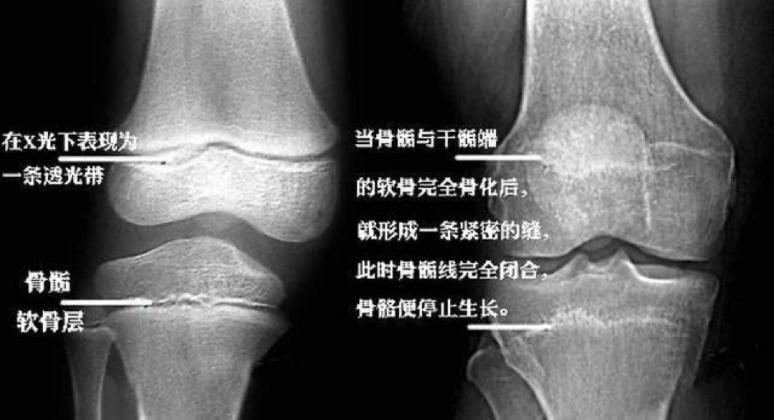

骨骺是骨在发育过程中,骨两端的软骨中出现的骨化点。而骨骺线,就是骨骺与干骺端之间的软骨, 在儿童的x光片上表现为一条较宽的透光带 。

当孩子的年龄增长时,骨骺线也会随之缩短,最终变成一条缝,自此骨骺线完全闭合,骨骼停止生长。